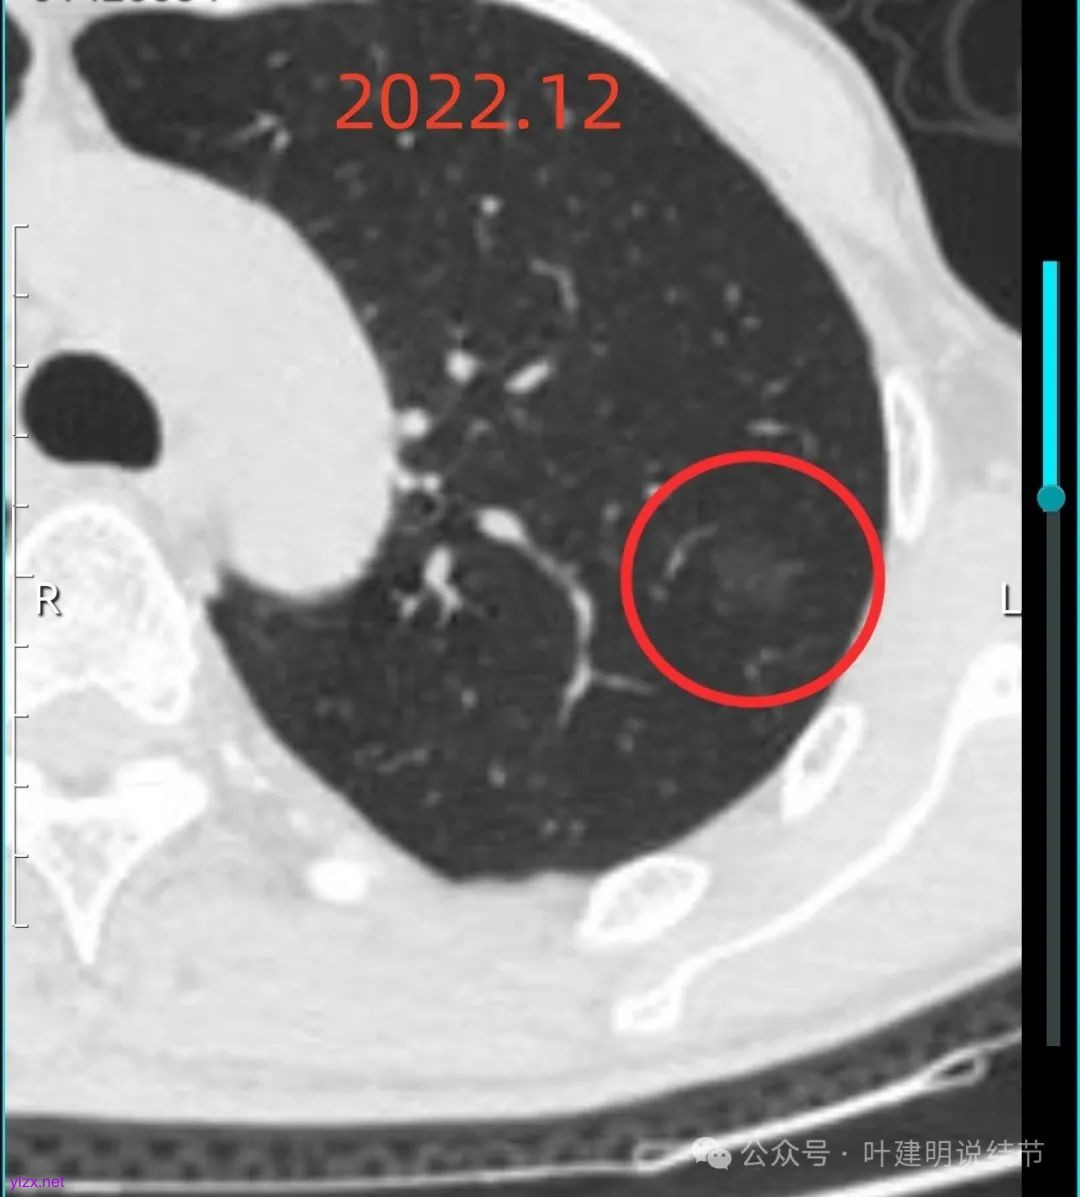

灶内出现了明显的实性成分,整体轮廓较清。

除了原血管进入外,另外角度也见到其他血管发出分支走向病灶,而且灶内密度不均,实性成分明显。

绿色的像是慢性炎,随访没有进展;红色的2022年12月开始是纯磨玻璃密度,但有小血管进入和整体轮廓较清,这种密度风险不高,但随访持续在的话,则要考虑肿瘤范畴,不典型增生或原位癌可能性大。再看2025年12月的,范围有所增大,磨玻璃部分密度仍很淡,但灶内出现实性成分,实性成分不太密实,稍显模糊。我觉得像微浸润性腺癌或原位癌伴肺泡塌陷可能性大。位置还好,病灶也不太小,若再增大进展切除范围更多些,我倾向单孔胸腔镜下局部楔形切了为妥。意见供参考!